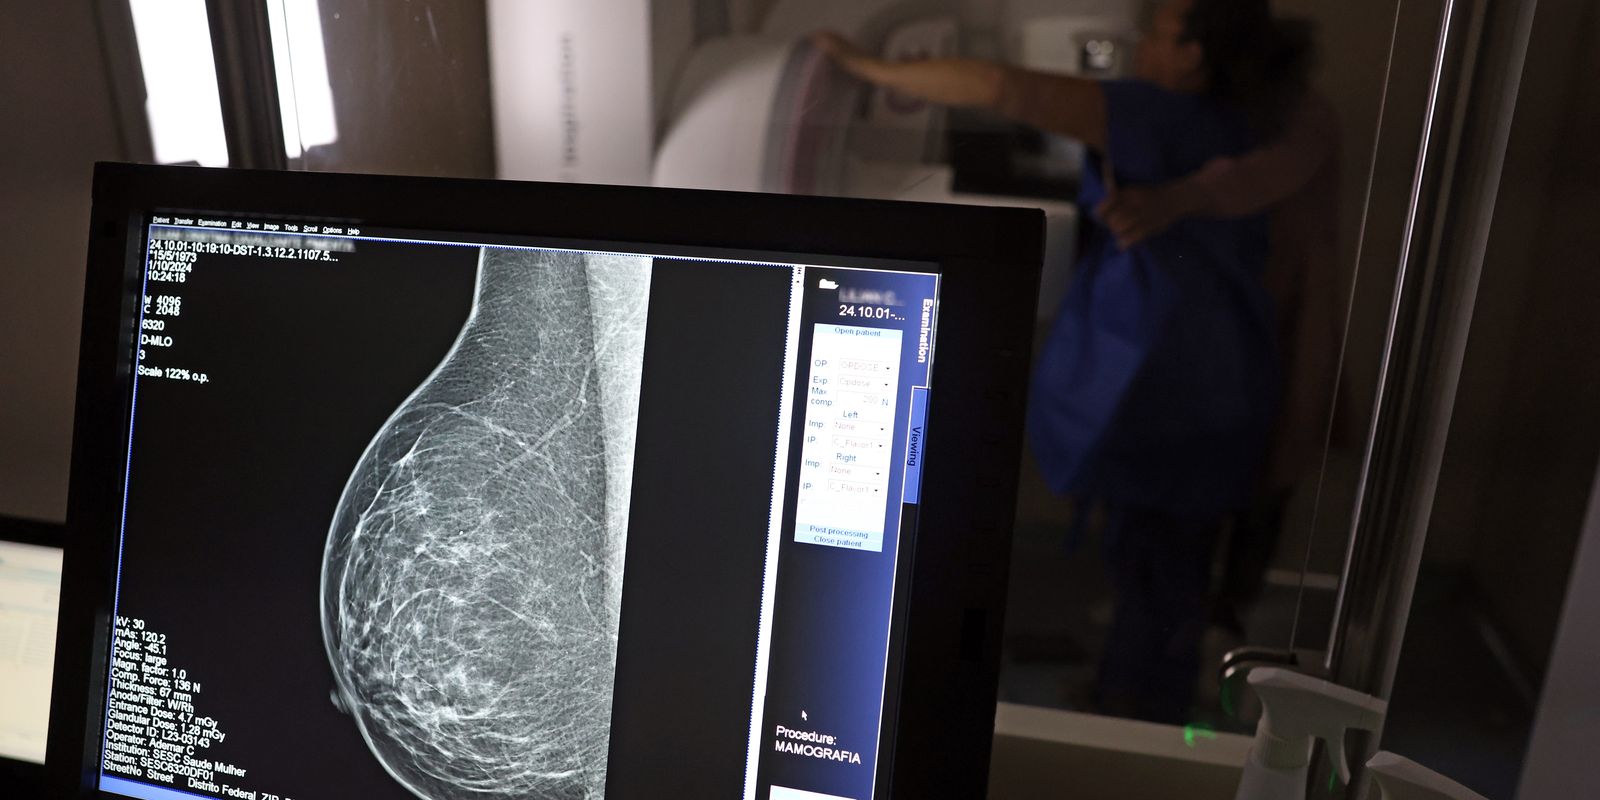

Ministério da Saúde passa a recomendar mamografia a partir dos 40 anos

O Ministério da Saúde passou a recomendar o acesso a mamografia, via Sistema Único de Saúde (SUS), para mulheres de 40 a 49 anos – mesmo que não haja sinais ou sintomas de câncer de mama. De acordo com a pasta, a faixa etária concentra 23% dos casos da doença, e a detecção precoce aumenta as chances de cura.

Até então, a orientação era que o exame fosse feito a partir dos 50 anos.

A medida faz parte de um conjunto de ações anunciadas nesta terça-feira (23) voltado para a melhoria do diagnóstico e da assistência. A recomendação para mulheres a partir dos 40 anos é que o exame seja feito sob demanda, em decisão conjunta com o profissional de saúde.

Outra medida anunciada é a ampliação da faixa etária para o rastreamento ativo – quando a mamografia é solicitada de forma preventiva a cada dois anos. A idade limite, até então, era 69 anos. Agora, passa a ser 74 anos. Dados do ministério revelam que quase 60% dos casos de câncer de mama estão concentrados entre 50 e 74 anos.

“A ampliação do acesso à mamografia aproxima o Brasil de práticas internacionais, como as adotadas na Austrália, e reforça o compromisso em garantir diagnóstico precoce e cuidado integral às mulheres brasileiras. O câncer de mama é o mais comum e o que mais mata mulheres, com 37 mil casos por ano”, reforçou a pasta.

Os números mostram que, em 2024, cerca de 4 milhões de mamografias para rastreamento e 376,7 mil exames diagnósticos foram realizados no SUS.